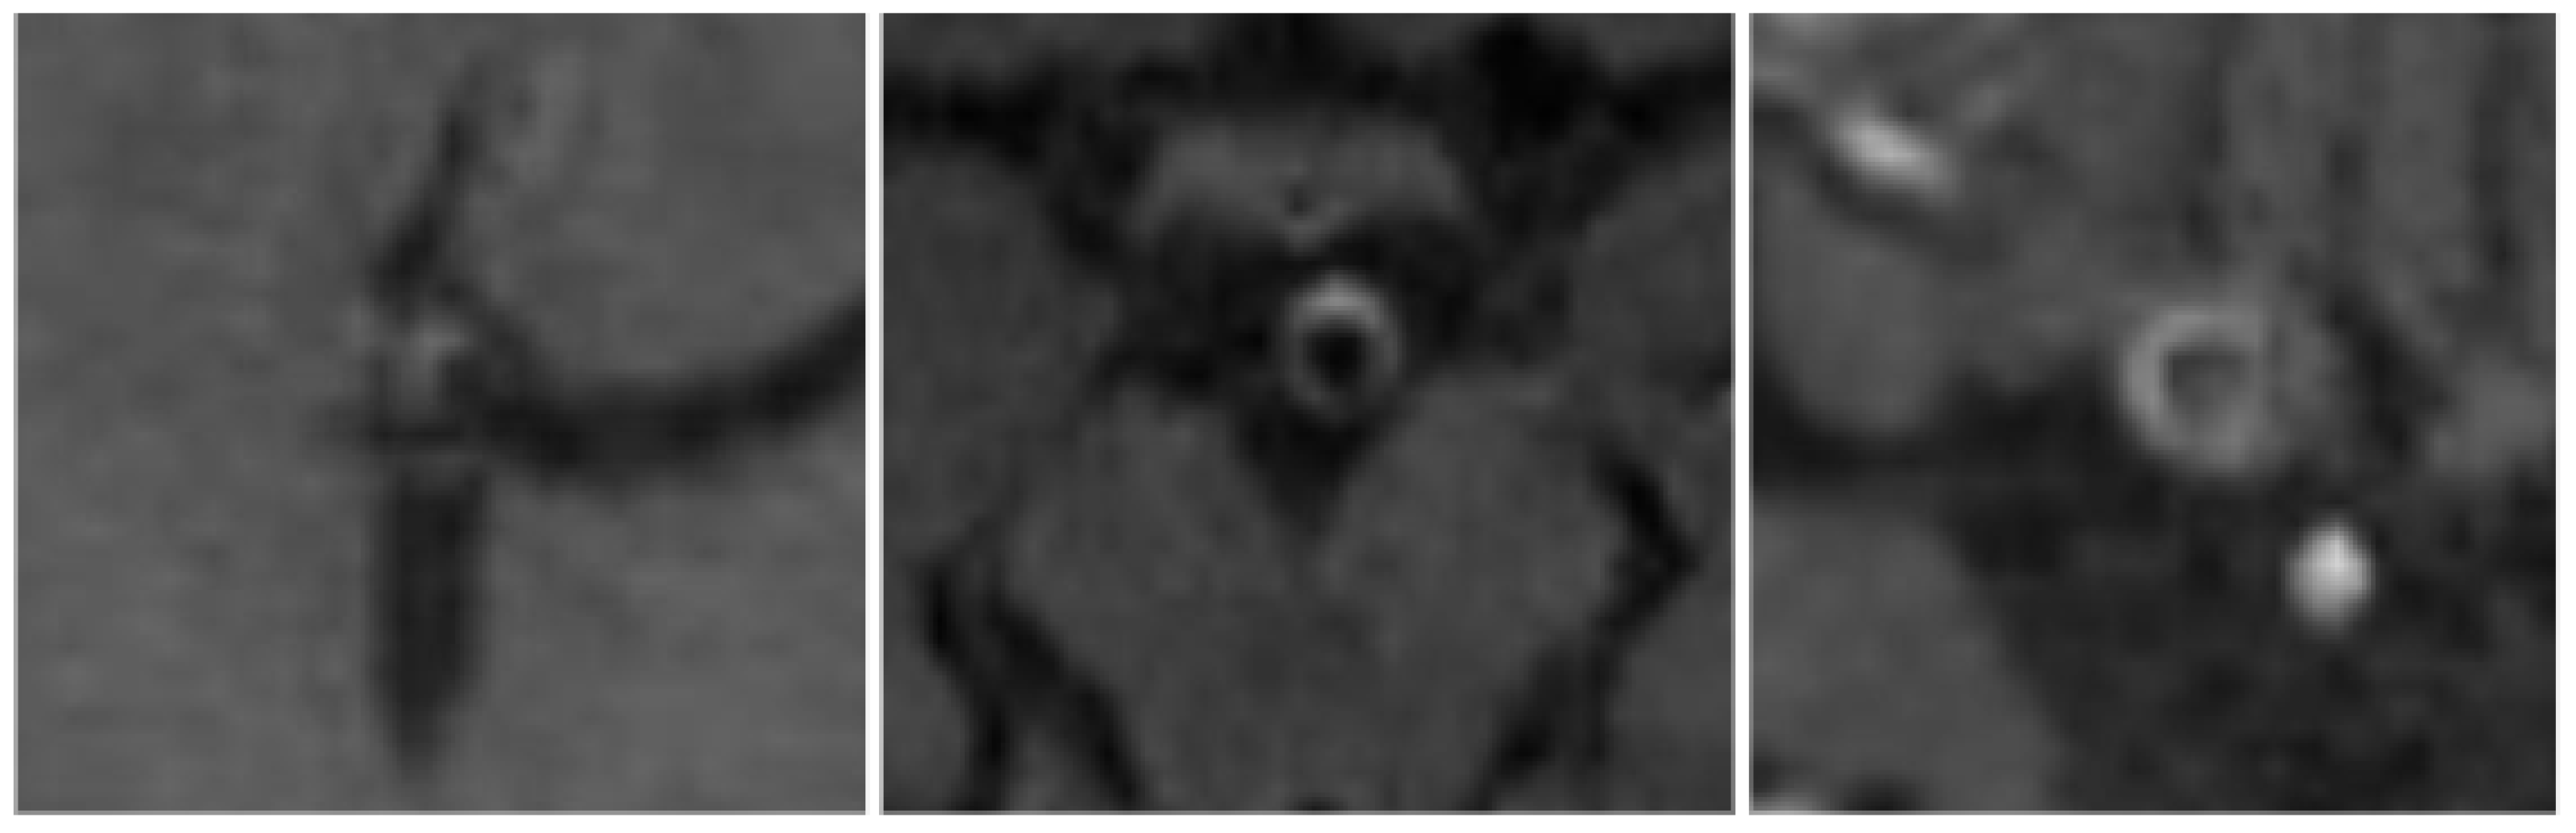

In this study, if present, AWE was categorized into 3 grades, based on the enhancement patterns and enhancement intensity, combined with thickening of the vessel wall of IAs in the follow up examinations after ET, as shown in Figure 1:

• Grade 1: Non – continuous enhancement

• Grade 2: Continuous linear enhancement without thickening of the aneurysmal wall

• Grade 3: Continuous linear enhancement with thickening of the aneurysmal wall

Figure 1. From left to right: Left: Grade 1 AWE in a middle cerebral artery Aneurysm, showing non - continuous arterial wall semilunar enhancement on the right ventral circumference. Middle: Grade 2 AWE in a basilar artery aneurysm showing continuous arterial wall enhancement without thickening of the vessel wall. Right: Grade 3 AWE in an internal cerebral artery Aneurysm with continuous enhancement and thickening of the vessel wall, the dorsolaterally located enhancing structure in the bottom right corner of the figure corresponds to the pituitary infundibulum.